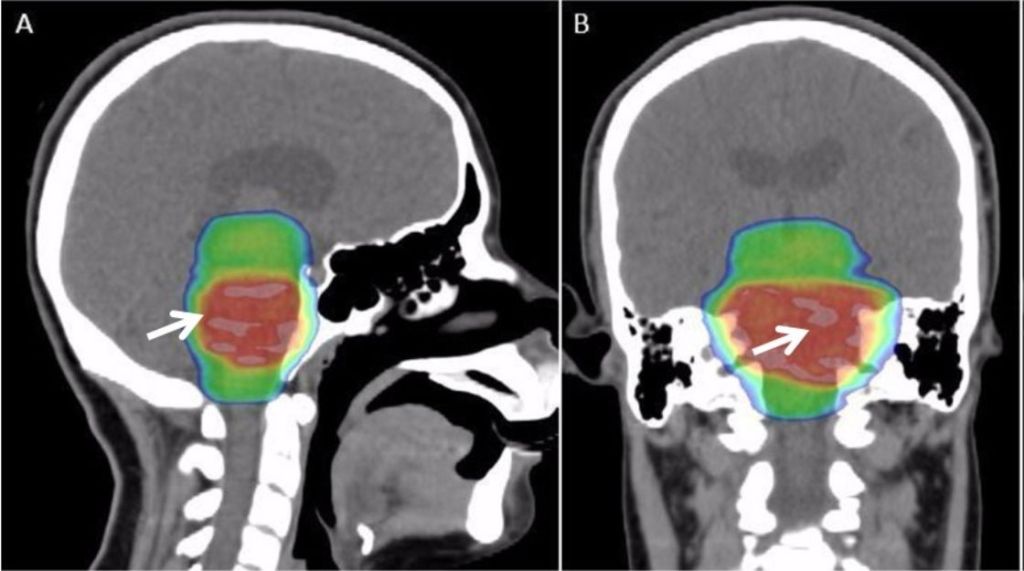

Contrairement à ce que l’on pourrait penser, le Gray (Gy) ne sert pas pour les activités BDSM. C’est en effet une unité dérivée du Système international utilisée pour estimer l’intensité d’un rayonnement. L’unité tient son nom de Louis Gray, un physicien britannique considéré comme père de la radiobiologie. Une exposition prolongée à 50 Gy entraîne une mort certaine. De fait, il est vital de compter avec précision les nuances de Gray lorsque l’on traite les tumeurs cérébrales avec des rayonnements.